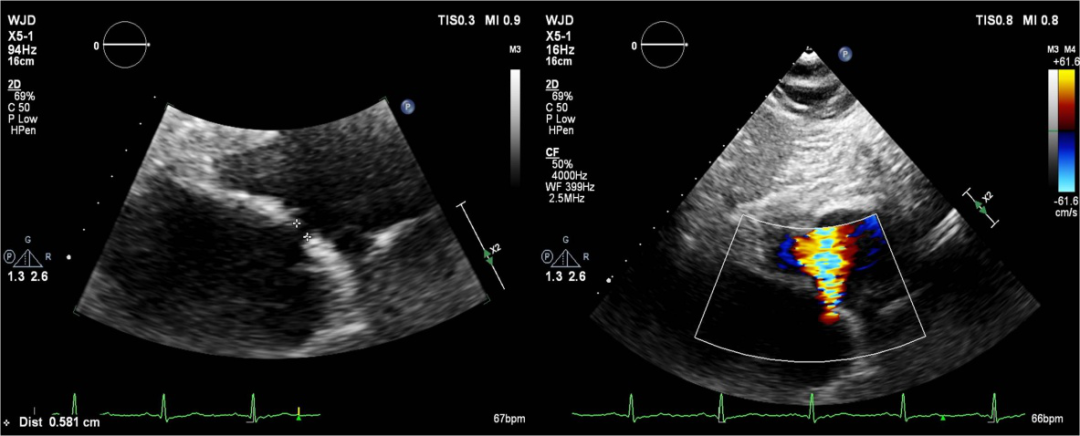

图解:超声心动图提示,术后通过所造房间隔瘘口,房水平可见左向右分流.